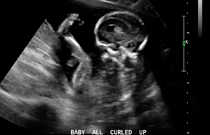

Từ tuần thai thứ 23-28

Đây là khoảng thời gian thực hiện siêu âm 4D tốt nhất. Bởi lúc này, hình dạng kết cấu và trạng thái vận động của thai nhi khá rõ ràng, hiệu quả hình ảnh tốt, có thể giúp phát hiện kịp thời các dị tật nghiêm trọng của thai nhi, chẩn đoán những bất thường về cấu tạo, như: hở hàm ếch, bất thường vùng não, hệ thống thần kinh, hệ thống gân cốt, hệ thống tim mạch, tứ chi...